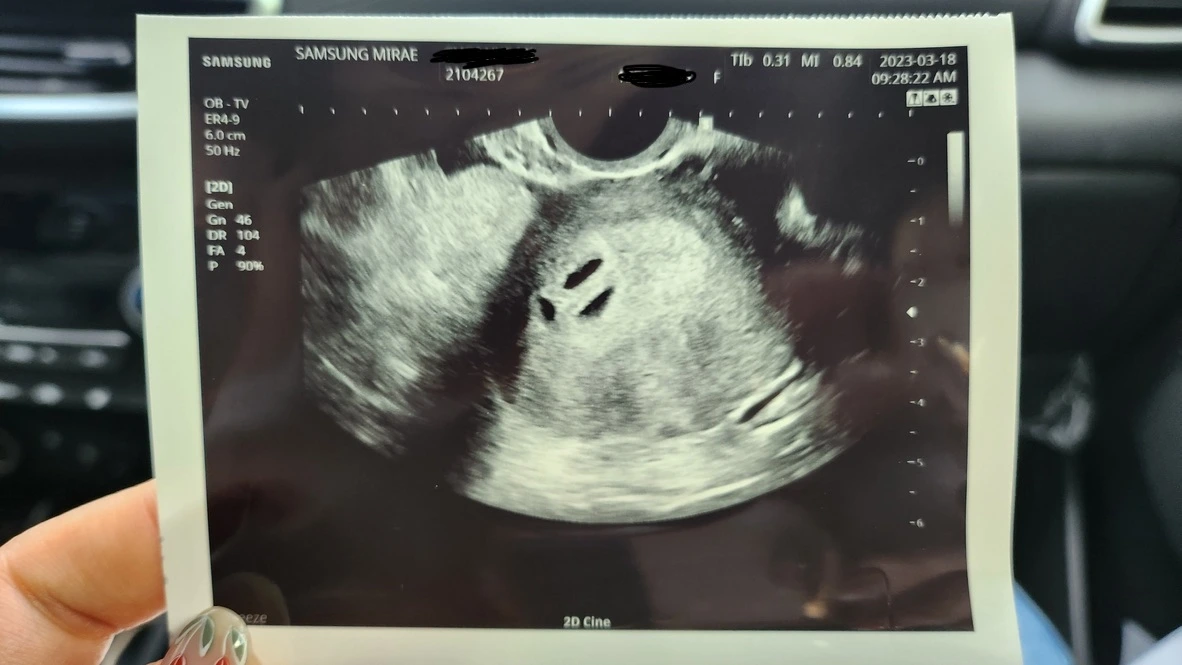

아기가 아내의 뱃속에 생겼다고 하지만 실제로 체감되지는 않았다. 가장 확실한 확인 방법은 바로 눈으로 직접 확인하는 것. 병원에 가서 초음파 사진을 보고 난 후에야 실감이 될 것 같았다. 떨리는 마음으로 초음파 영상을 확인했을 때 현장에 있는 모두가 놀랐다. 1개도 만나기 어렵다는 아기집이 3개나 있었다. 의사 선생님도 놀라움과 황당한 표정을 섞으며 세 쌍둥이라는 소식을 전했다.